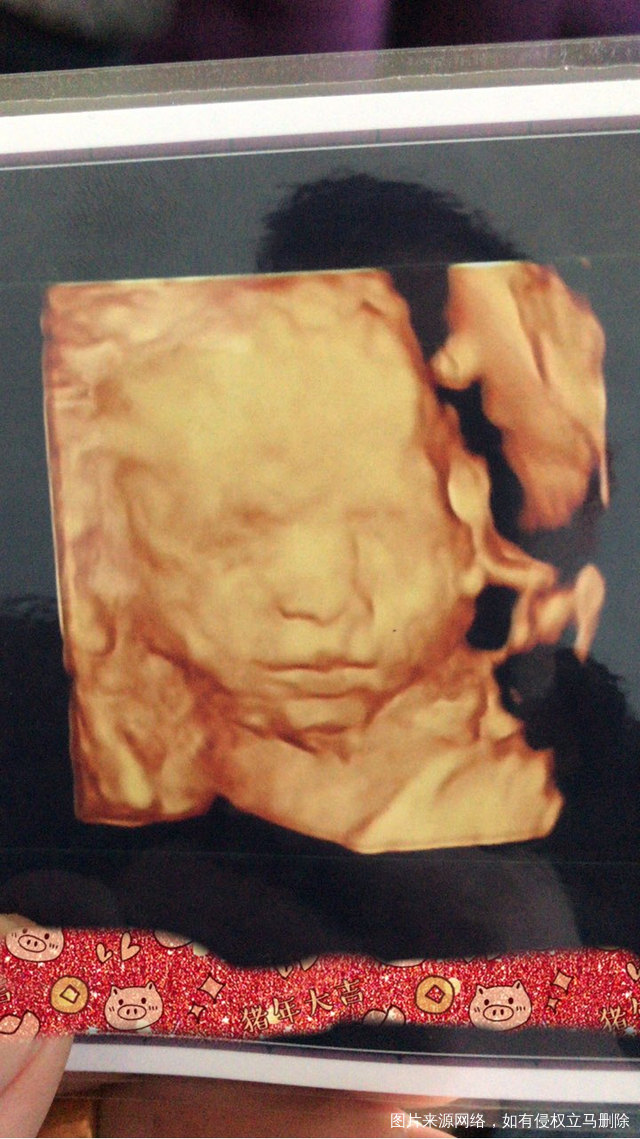

第一次看见宝宝这么清晰的面部 好开心哦 [大笑][大笑][大笑] 四维这是在妈妈肚子里第一张照片